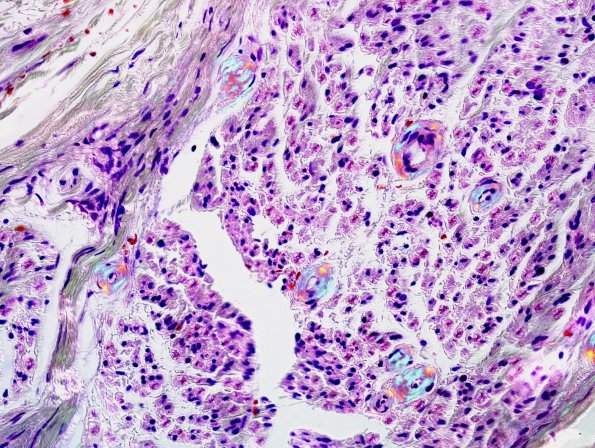

Polarization of image #4C1. (Congo red)